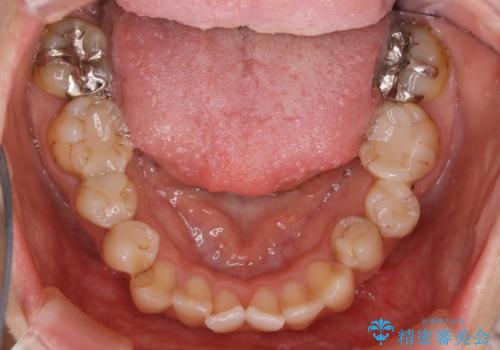

- 前歯のガタつきと噛み合わせの改善を希望してご来院されました。

目立たない装置での矯正治療をとのことでインビザラインを用いた非抜歯矯正を行うこととなりました。

歯のガタつきをとるためのスペース作りの方法の一つにディスキング(IPR)という方法があります。

歯と歯の間を一ケ所あたり最大0.5mmまでの範囲内で削ることで歯自体が少し小さくなり、それにより作られるスペースを数ヶ所分合わせることで合計で数mmの大きなスペースが作れるという方法です。